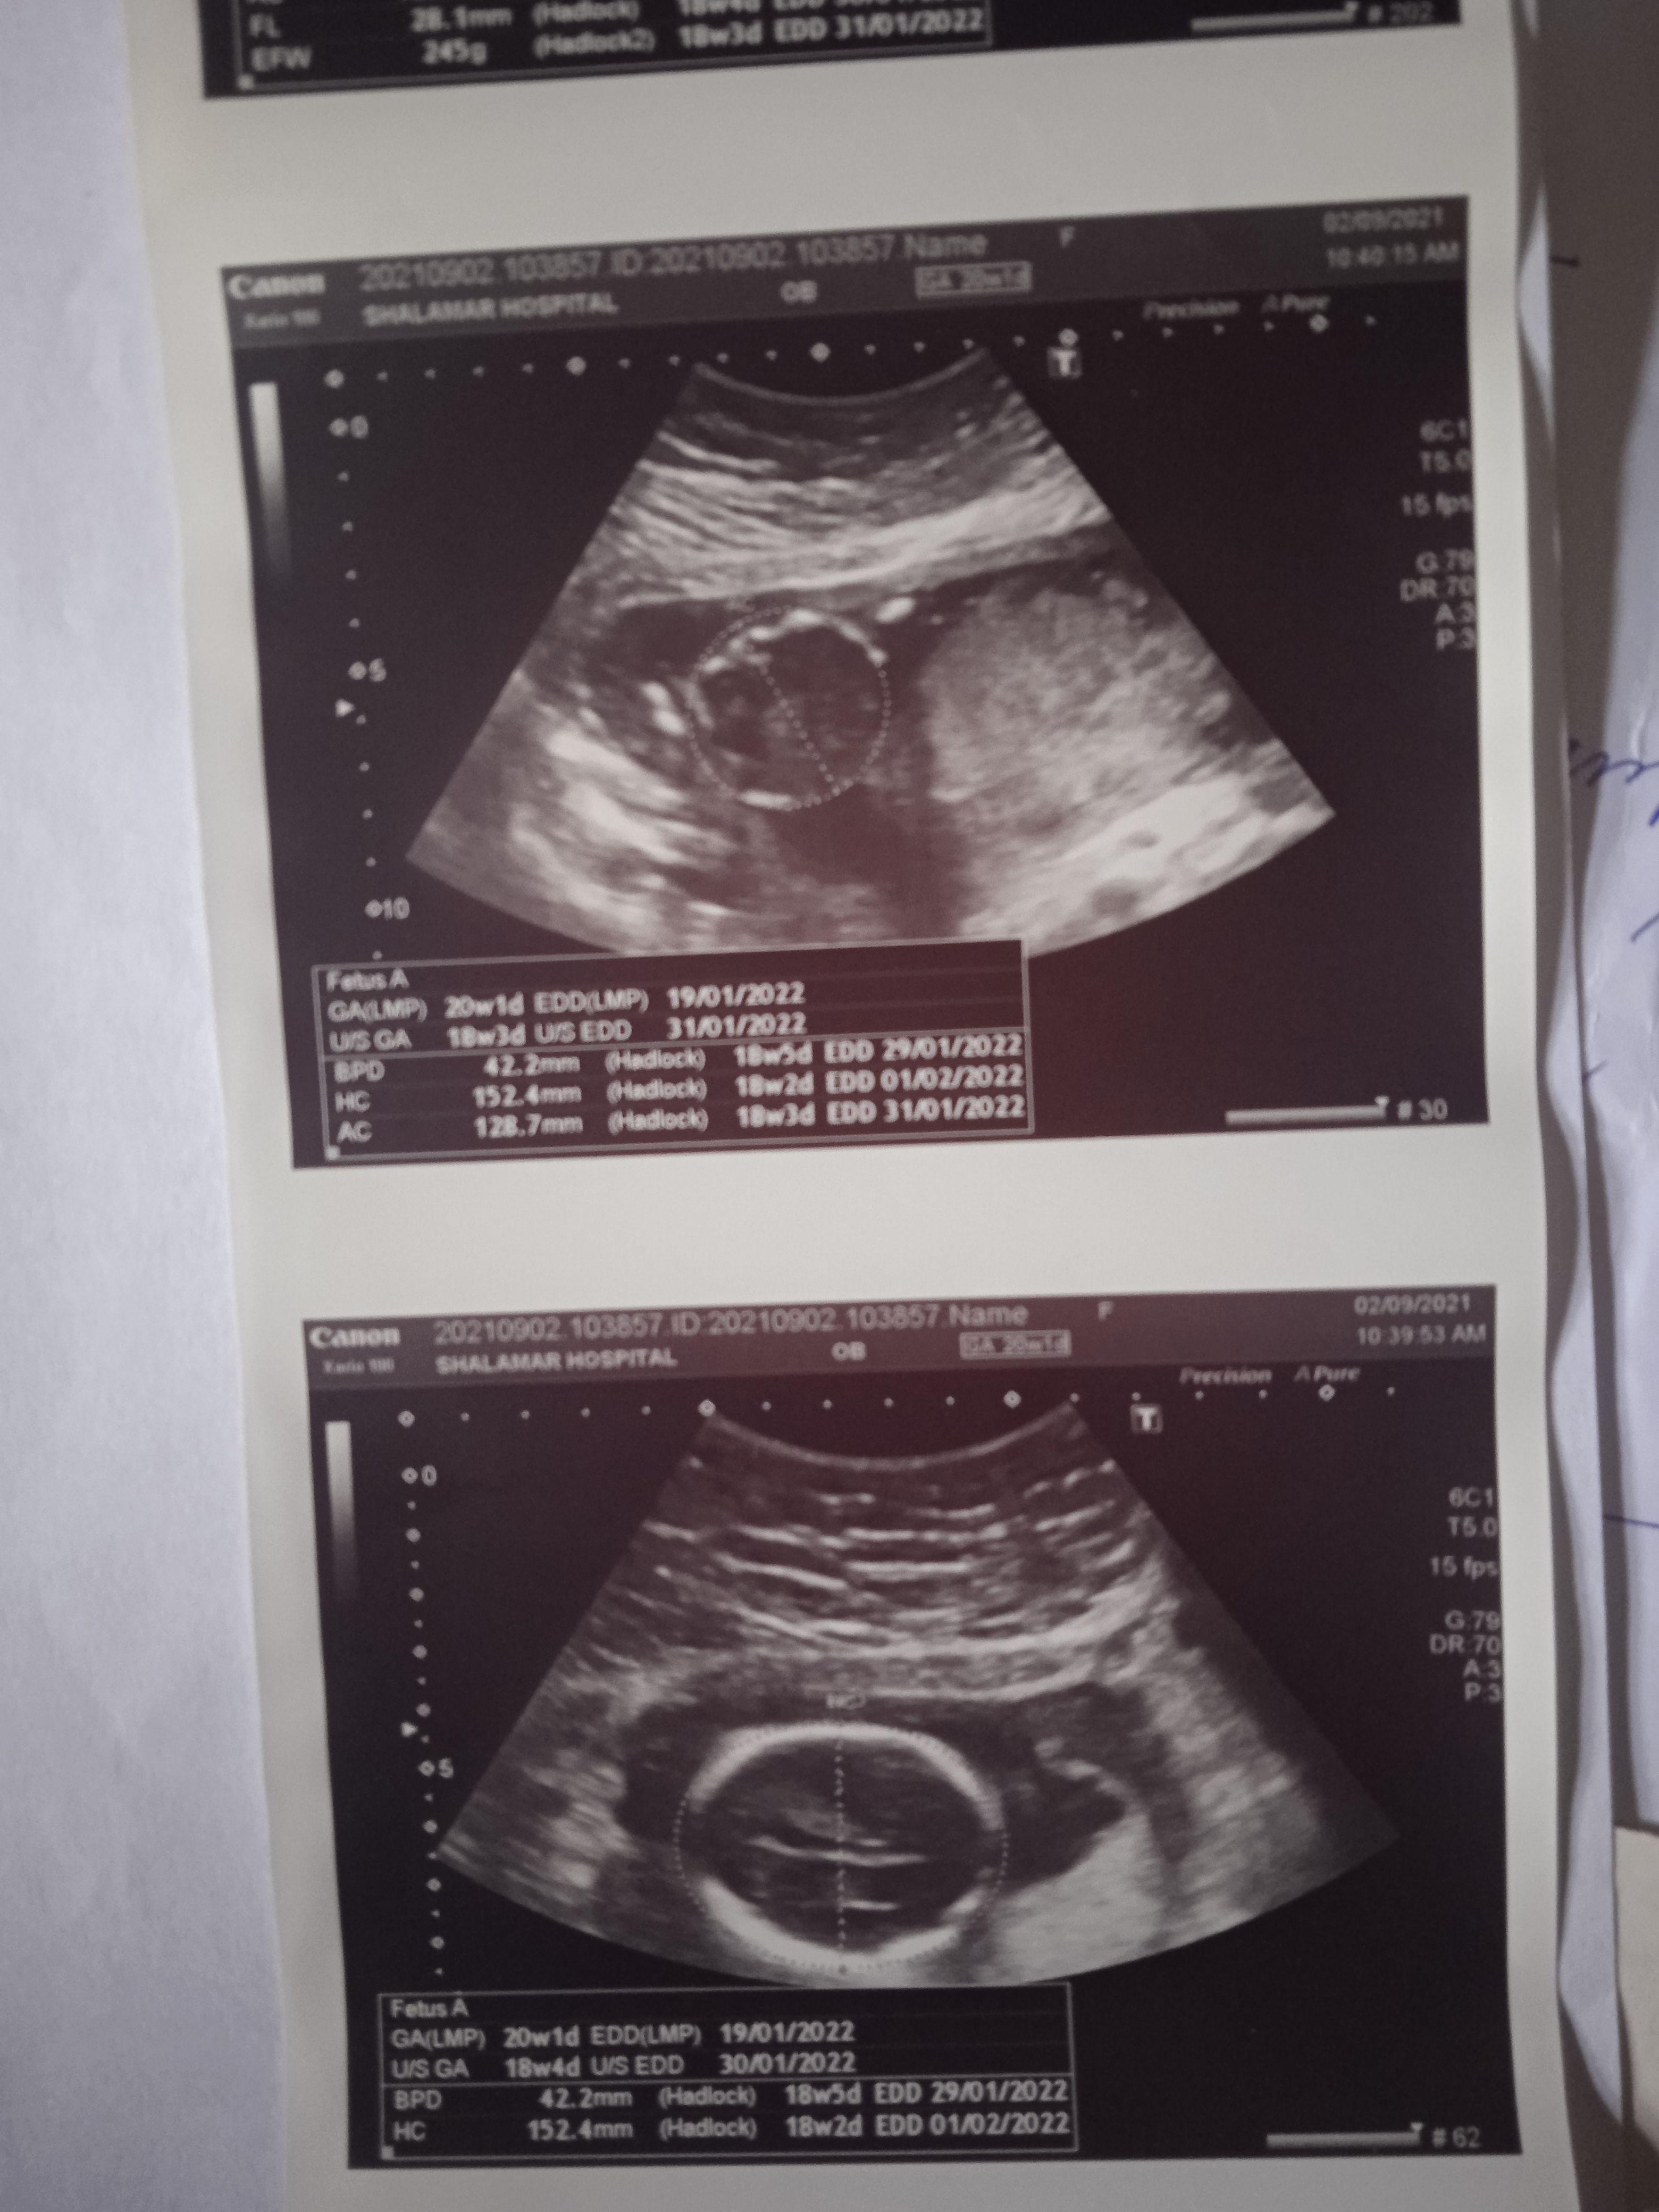

Please check the pics below.

And tell me about my baby gander.

Here is my altrasound report

Plz tell me gender of my baby plz

Here is altrasound report

Please see that report.

Anyone please let me know my baby's gender

I have uploaded my altrasound report